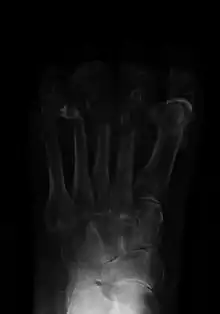

![]() | |

Osteomyelitis of the 1st toe | |

Radiographs and CT are the initial method of diagnosis, but are not sensitive and only moderately specific for the diagnosis. They can show the cortical destruction of advanced osteomyelitis, but can miss nascent or indolent diagnoses.[23]

Confirmation is most often by MRI[24]. The presence of edema, diagnosed as increased signal on T2 sequences, is sensitive, but not specific, as edema can occur in reaction to adjacent cellulitis. Confirmation of bony marrow and cortical destruction by viewing the T1 sequences significantly increases specificity. The administration of intravenous gadolinium-based contrast enhances specificity further. In certain situations, such as severe Charcot arthropathy, diagnosis with MRI is still difficult.[23] Similarly, it is limited in distinguishing avascular necrosis from osteomyelitis in sickle cell anemia.[25]

Diagnosis of osteomyelitis is often based on radiologic results showing a lytic center with a ring of sclerosis.[13] Culture of material taken from a bone biopsy is needed to identify the specific pathogen;[27] alternative sampling methods such as needle puncture or surface swabs are easier to perform, but cannot be trusted to produce reliable results.[28][29]